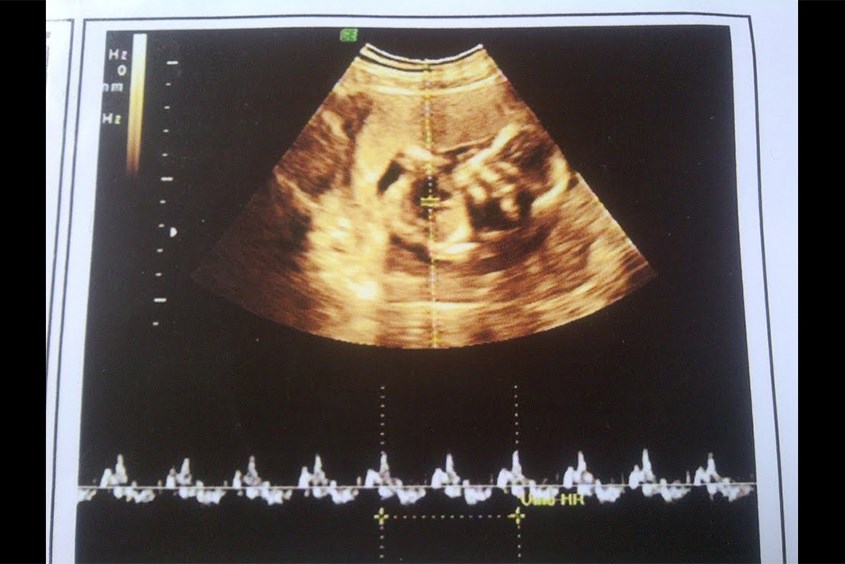

Hình ảnh siêu âm thai nhi 7 tuần tuổi

Thai 7 tuần là giai đoạn quan trọng trong sự phát triển tim thai. Bác sĩ có thể xác định được nhịp tim rõ ràng nhất khi siêu âm thai qua đường âm đạo. Ở khoảng thời gian này, tim đã chia thành 2 ngăn trái - phải, nhịp tim thai trung bình sẽ khoảng 90 - 100 nhịp/phút và tăng dần trong những tháng sau đó.

Siêu âm tim thai nhi 7 tuần tuổi

Nhịp tim thai 7 tuần tuổi sẽ khoảng 90 - 100 nhịp/phút